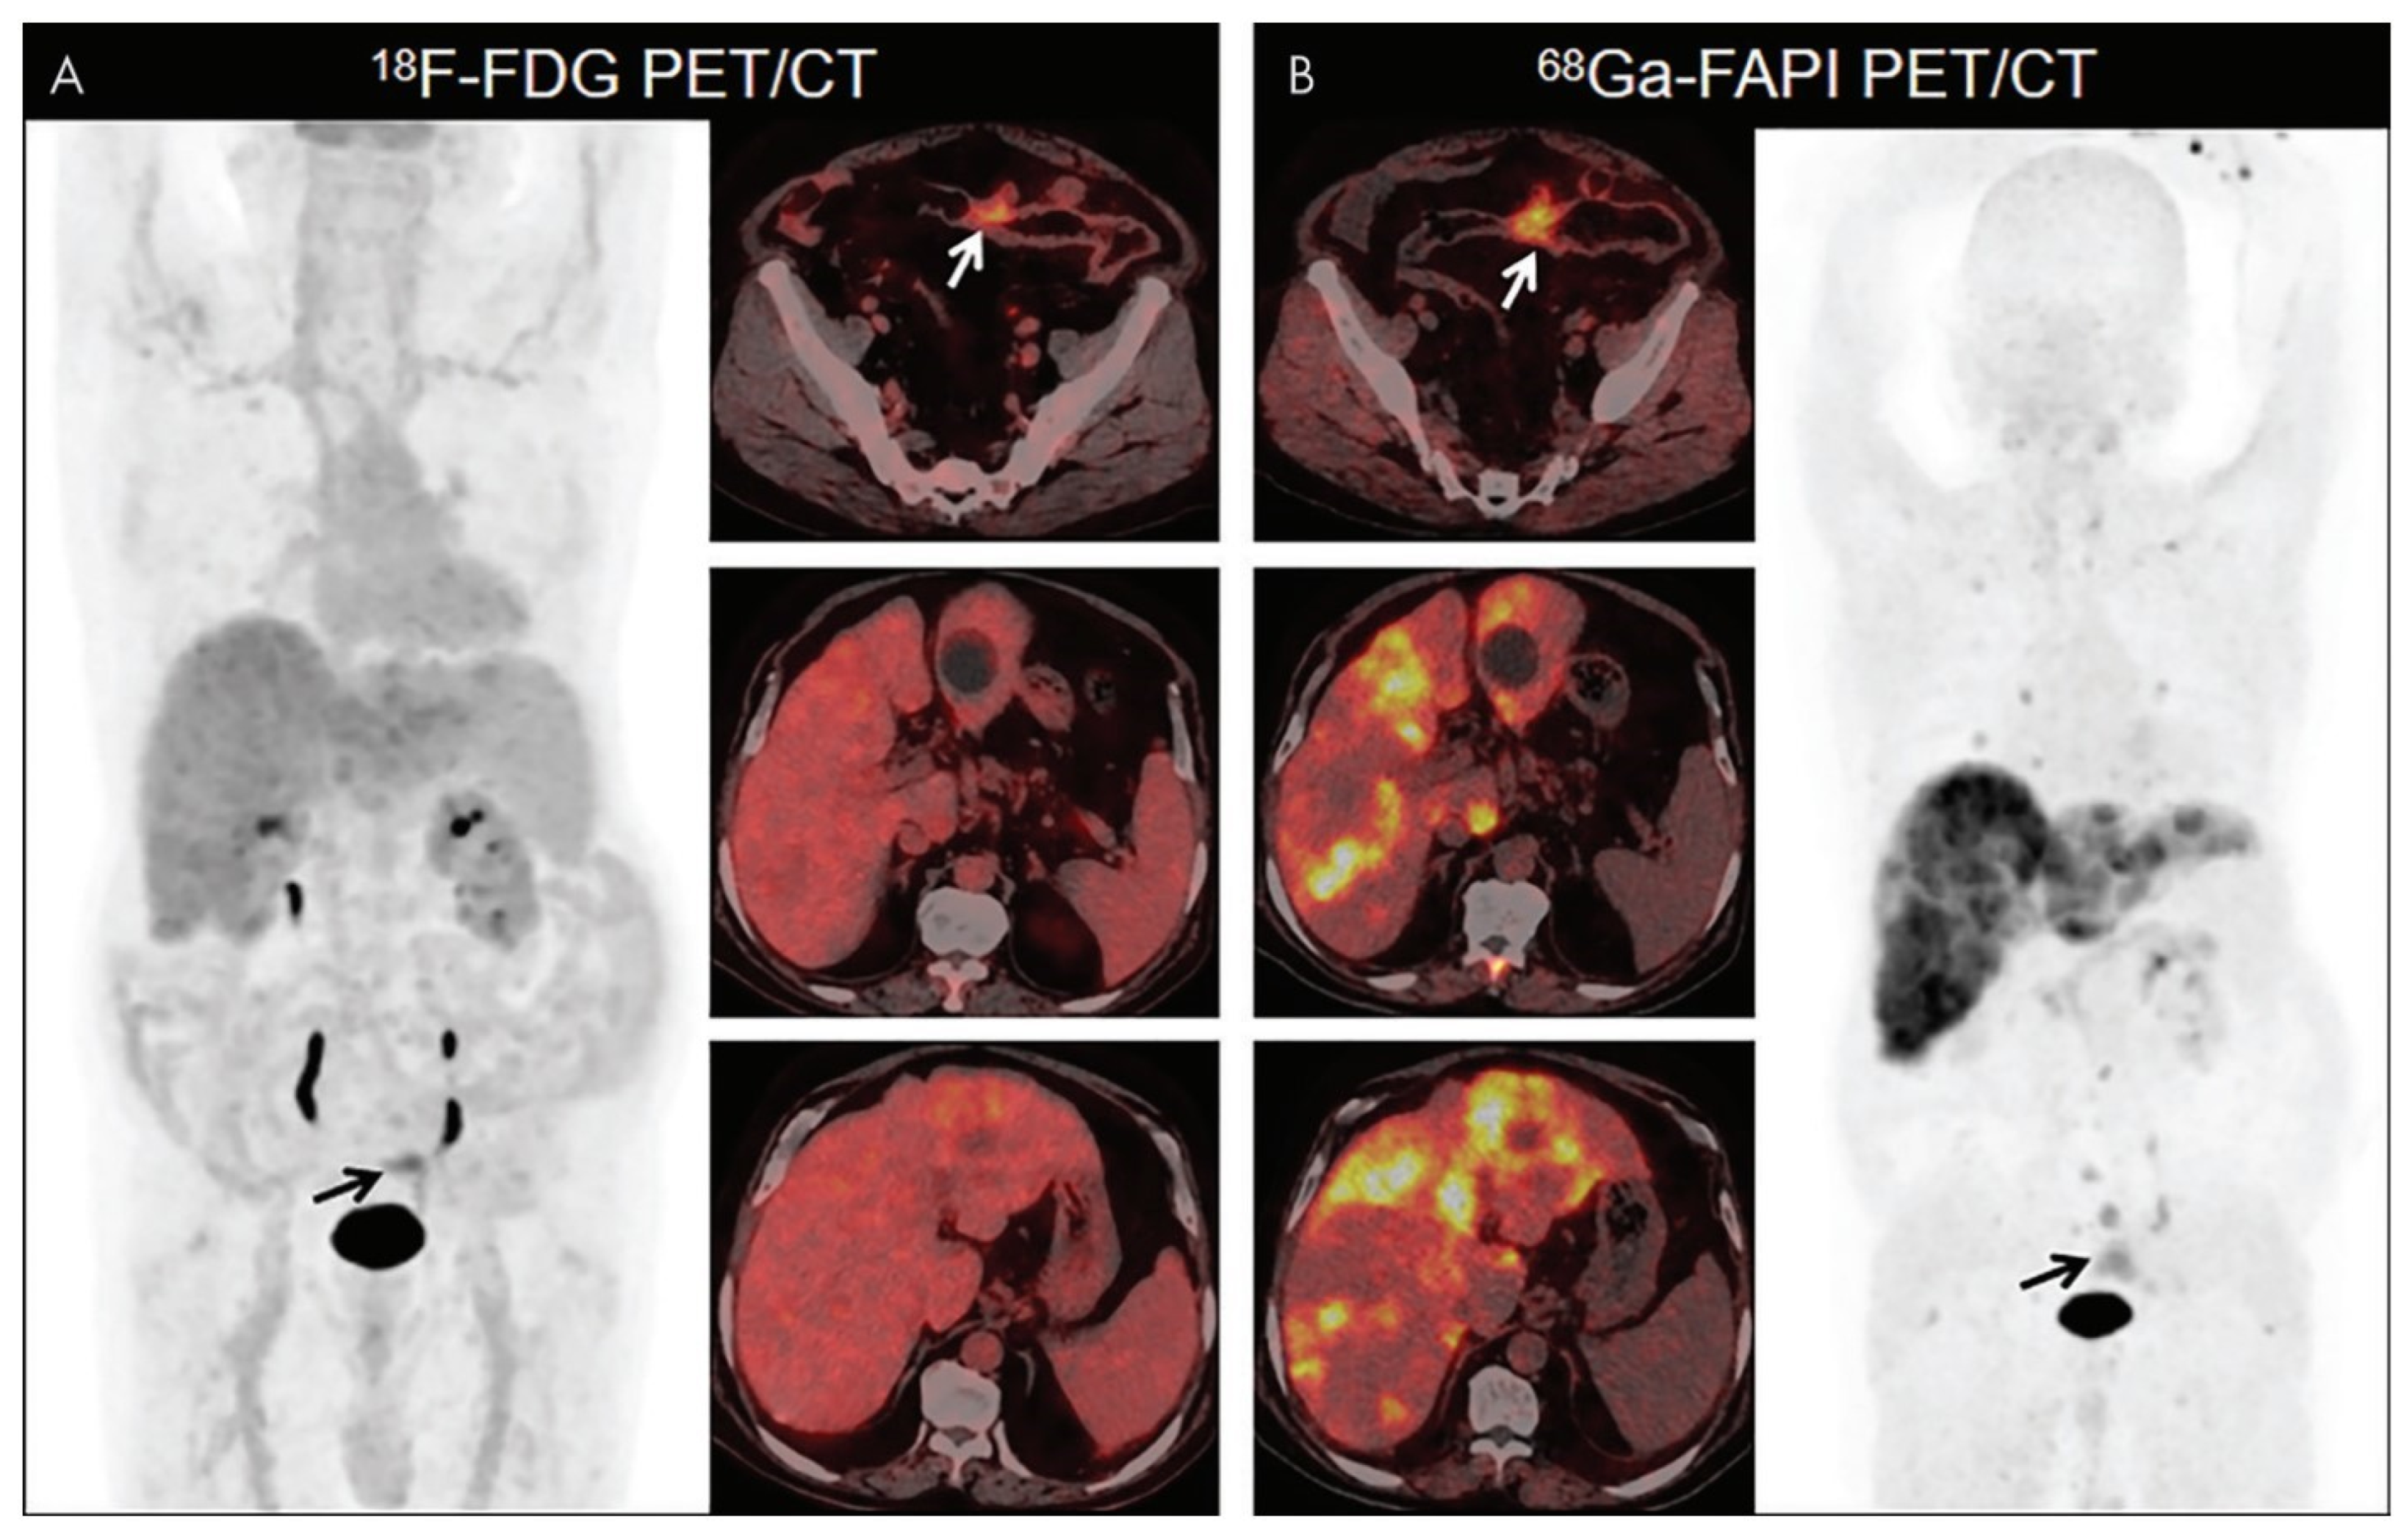

- Pang, Y.; Zhao, L.; Luo, Z.; Hao, B.; Wu, H.; Lin, Q.; Sun, L.; Chen, H. Comparison of 68Ga-FAPI and 18F-FDG Uptake in Gastric, Duodenal, and Colorectal Cancers. Radiology 2021, 298, 393–402. [Google Scholar] [CrossRef]

- Chen, H.; Pang, Y.; Wu, J.; Zhao, L.; Hao, B.; Wu, J.; Wei, J.; Wu, S.; Zhao, L.; Luo, Z.; et al. Comparison of [68Ga]Ga-DOTA-FAPI-04 and [18F] FDG PET/CT for the diagnosis of primary and metastatic lesions in patients with various types of cancer. Eur. J. Nucl. Med. Mol. Imaging 2020, 47, 1820–1832. [Google Scholar] [CrossRef] [PubMed]

| Pang et al. | 2021 | Article | 68Ga-FAPI was superior to 18F-FDG in the detection of colorectal cancer primary and metastatic sites, showing higher uptake in most primary and metastatic sites. |